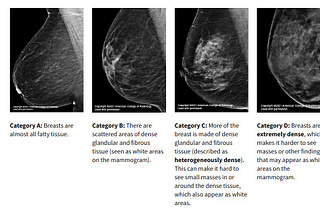

My mammogram says I have dense breasts

A common finding, and a mutual conundrum